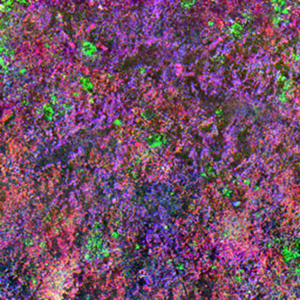

图2:1744 cm⁻¹与1060 cm⁻¹波数PiFM图像共同凸显磷酸化蛋白质的相同聚集体

图1展示了来自TG样本(阿尔茨海默病模型)的三组PiF-IR光谱(浅绿、蓝、紫色)及对照组(非阿尔茨海默病)的PiF-IR光谱;插图为脑切片AFM形貌图,并标注光谱采集位点。TG样本的浅绿与蓝色光谱与对照组光谱相似,均显示显著的酰胺I带(1660 cm⁻¹)与酰胺II带(1550 cm⁻¹)特征峰,以及较弱强度的1740 cm⁻¹(脂质酯基C=O伸缩振动)、1243 cm⁻¹(磷脂PO₂⁻不对称伸缩振动)和1065 cm⁻¹(磷脂对称伸缩振动)特征峰。在TG样本类聚集体特征处采集的紫色PiF-IR光谱显示1740、1243及1065 cm⁻¹处峰强度显著增强,而酰胺峰强度减弱。图2展示了1744 cm⁻¹与1060 cm⁻¹波数采集的PiFM图像及同区域AFM形貌图。可见两幅PiFM图像凸显相同特征结构,该现象很可能源于磷酸化修饰;需注意纳米尺度特征在兩幅图像中均得到良好重现。目前难以判断PiFM特征是否与形貌特征存在关联性。